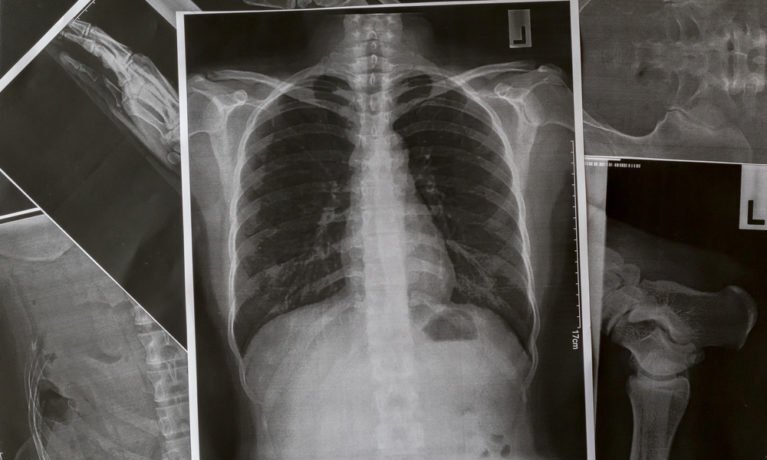

Theo Reader’s Digest, thuyên tắc phổi là một căn bệnh nghiêm trọng xảy ra khi cục máu đông làm tắc nghẽn mạch máu trong phổi. Cục máu đông thường phát triển ở một bộ phận của cơ thể (thường là chân) và sau đó theo máu đến phổi.

Theo Viện Y tế Quốc gia (NIH), một nhóm người sẽ phát triển huyết khối và trở thành tắc mạch. Phổi bao gồm béo phì, ung thư, bệnh tim, bệnh phổi hoặc bệnh xương hông, gãy xương chân.